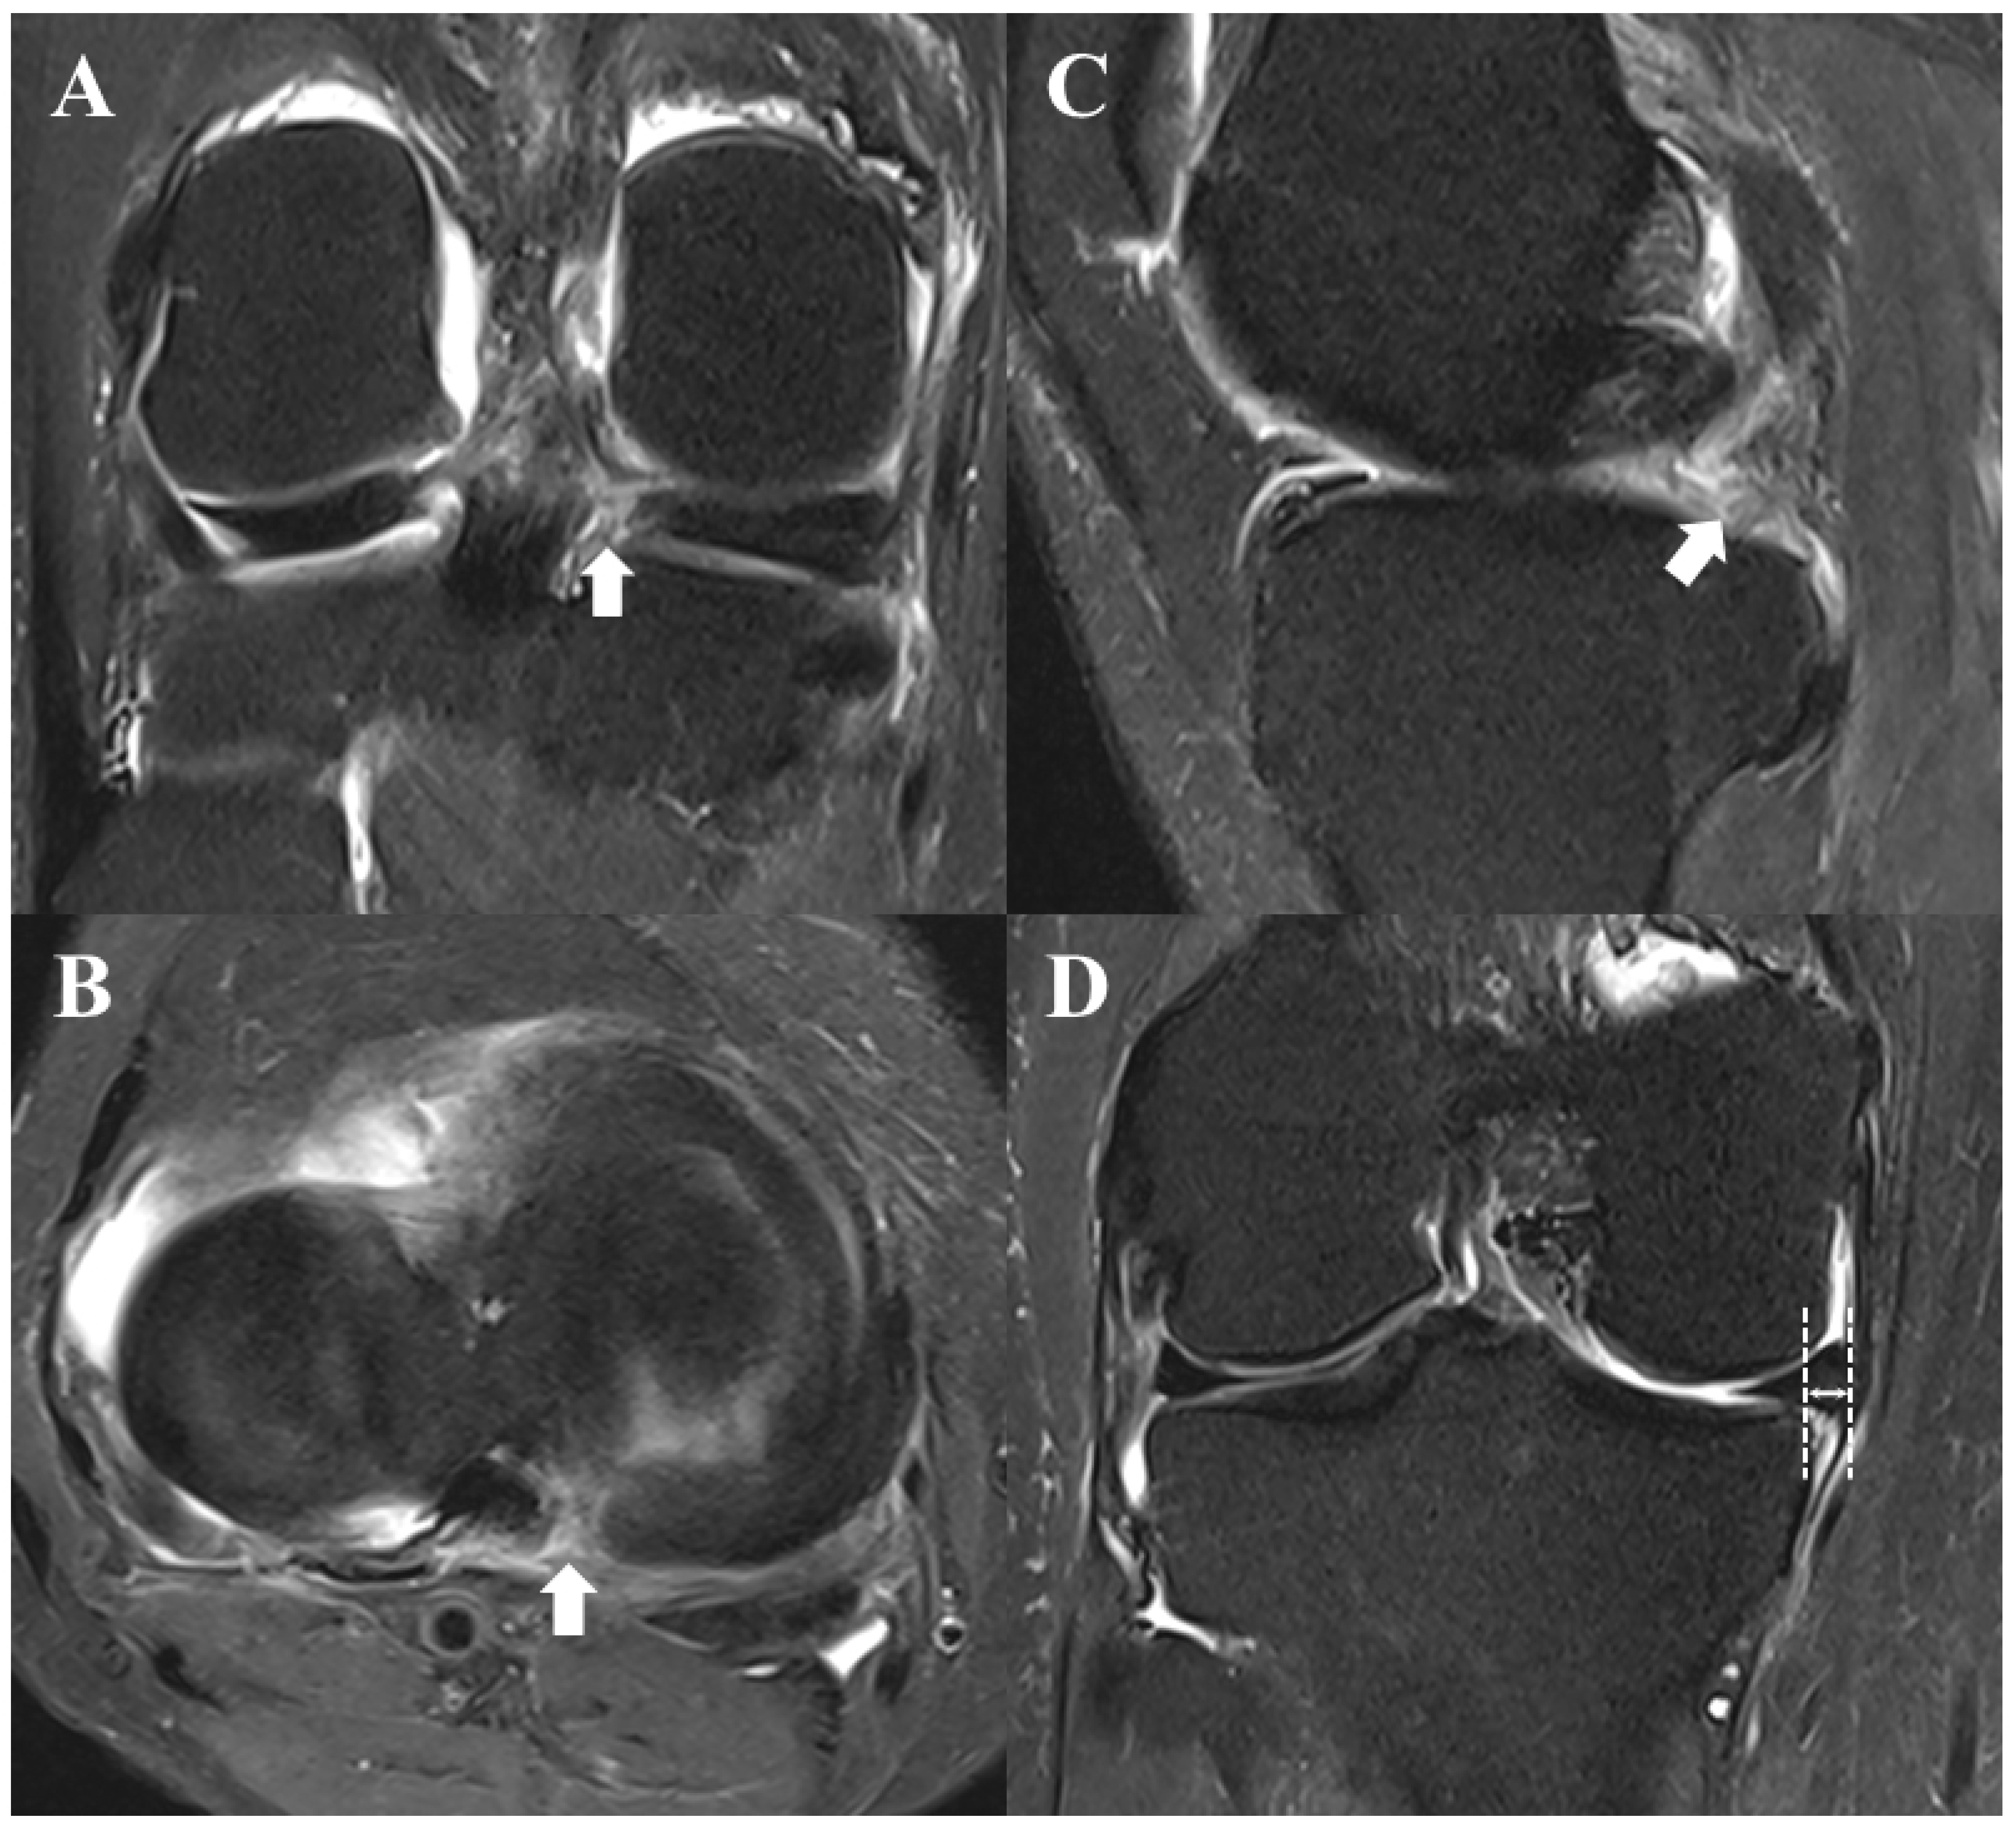

- Choi, S.H.; Bae, S.; Ji, S.K.; Chang, M.J. The MRI findings of meniscal root tear of the medial meniscus: Emphasis on coronal, sagittal and axial images. Knee Surg. Sport. Traumatol. Arthrosc. 2012, 20, 2098–2103. [Google Scholar] [CrossRef] [PubMed]

- Lee, Y.G.; Shim, J.C.; Choi, Y.S.; Kim, J.G.; Lee, G.J.; Kim, H.K. Magnetic resonance imaging findings of surgically proven medial meniscus root tear: Tear configuration and associated knee abnormalities. J. Comput. Assist. Tomogr. 2008, 32, 452–457. [Google Scholar] [CrossRef] [PubMed]